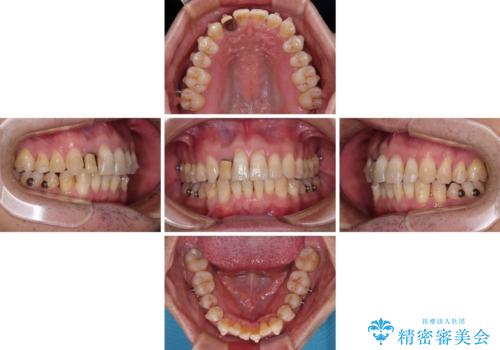

- 矯正装置

- インビザライン

- 治療期間

- 1年2ヶ月